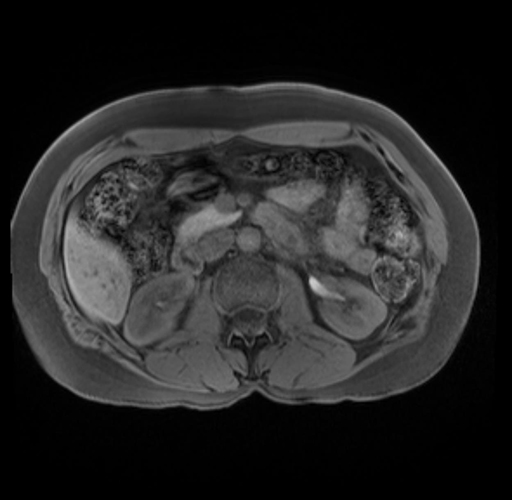

Imaging Analysis

Look through the patient's CT scan to identify any areas of concern for the necessary procedure.

Based on your CT findings, which issue(s) are present and would give reason for "planned slowing down moment(s)" in this case?

Considering a standard distal pancreatectomy procedure, what step(s) of the operation would you do differently in this case?